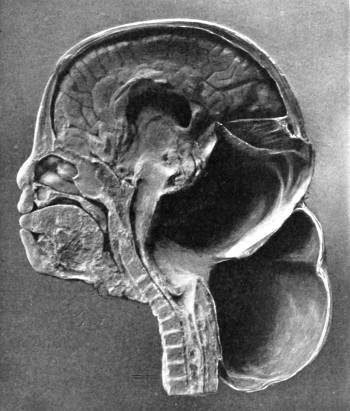

Fig. 20. An Occipital Cephalocele. (For further description, see text.)

1. Occipital cephaloceles—the commonest variety—occupy, anatomically, two positions (1) between the two lower segments of the occipital bone (inferior occipital cephaloceles), often involving the foramen magnum and sometimes complicated by a condition of cervical spina bifida, and (2) between the two upper segments of the occipital bone (superior occipital cephaloceles), occasionally involving the posterior fontanelle.

The tumour may possess a broad base or may be definitely pedunculated. In the former instance the gap in the bone may be of considerable size and the margins everted: in the latter case, the hole may be quite small.

The deformity is frequently associated with other congenital defects—hydrocephalus, microcephalus, spina bifida, hare lip, hernia, and talipes.

Sincipital cephaloceles are usually quite small, but the occipital variety and those situated in[35] the region of the anterior fontanelle frequently attain a great size (see Figs. 20-22).

Fig. 22. An Occipital Cephalocele. (For further description, see text.)

The following case serves to illustrate some of these facts:[9]—

The child was 3 months old, and presented a tumour, the size of an orange, situated between the occipital protuberance and the nape of the neck. The mass was pedunculated, the stalk being about the size of a four-shilling piece in diameter. It was soft, translucent, irreducible, and swelled up on coughing. An attempt at removal was carried out, and, after incising the outermost layers, three ounces of cerebro-spinal fluid escaped. A second tumour was then found occupying the base of the swelling. This was also punctured, more fluid escaping. Both sacs were cut away and the wound sewn up. Death occurred on the third day, preceded by convulsions, retraction of the head and neck, and high fever. The autopsy showed that the fontanelles were widely open, the anterior measuring 4 inches from side to side and 21⁄2 from before backwards. The bones of the vault were markedly thinned. In the subdural space there was a quantity of fluid, and the cerebral substance was soft and diffluent, the convolutions flattened, and the ventricles distended. There was a broad gap in the occipital bone, extending downwards into the foramen magnum, and in this situation the cerebellum had bulged backwards into the protruding mass. (See Fig. 22).